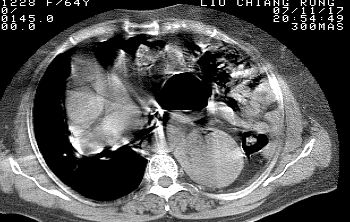

标题: CT10753:女, 64岁 隔疝 [打印本页]

标题: CT10753:女, 64岁 隔疝

女, 64岁 三十年前胸部外伤史, 间断胸闷,

典型左侧膈疝,疝出物为胃和大网膜,纵隔右移

同意左侧膈疝,不过,有过外伤史,左肺有受压征象,同时有胸膜增厚。